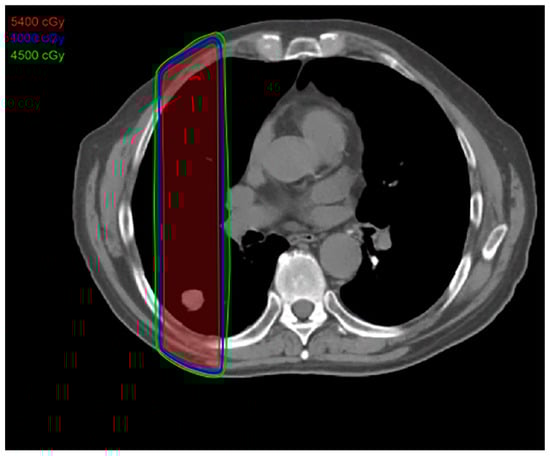

2.6. Proton Therapy